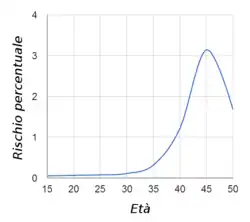

No se conocen con exactitud las causas que provocan el exceso cromosómico. Sin embargo, los factores de riesgo que los padres hayan concebido un hijo con síndrome de Down, son que cualquiera de los padres sea portador de la translocación genética para el síndrome de Down, y la edad avanzada de la madre. Aunque haya riesgo en cualquier edad, la probabilidad de concebir un hijo con síndrome de Down aumenta gradualmente después de los 35 años, debido a que el accidente genético de la división cromosómica anormal es más común en los óvulos más antiguos, aun así, la mayoría de los niños con síndrome de Down tienen madres jóvenes, simplemente porque las mujeres menores de 35 tienen muchos más hijos que las mayores.[1] Las personas con síndrome de Down tienen mayor probabilidad de padecer algunas enfermedades con respecto al resto de la población, especialmente de corazón, aparato digestivo y sistema endocrino debido al exceso de proteínas sintetizadas por el cromosoma de más. Los avances actuales en el descifrado del genoma humano están revelando algunos de los procesos bioquímicos subyacentes a la discapacidad intelectual, pero en la actualidad no existe ningún tratamiento farmacológico que haya demostrado que mejora las capacidades intelectuales de estas personas.[2][3][4][5][6]

Parece existir una relación estadística (sin que se conozcan los mecanismos) entre algunas enfermedades maternas como Hepatitis, Mycoplasma hominis tipo 1, Herpes simple tipo II y Diabetes[20] y un aumento en la incidencia de aparición de SD; No obstante esa relación estadística no es tan intensa como en el caso de la edad materna. Algún autor[21] también ha relacionado la baja frecuencia coital así como el uso de anovulatorios y espermicidas con la aparición del síndrome.

La probabilidad de tener un hijo con SD es mayor a la media para aquellos padres que han tenido otro previamente. Típicamente la probabilidad de tener otro hijo con SD en cada embarazo subsiguiente es de una por cada cien recién nacidos vivos. Esto hay que ponderarlo para cada caso con el riesgo propio de la madre según su edad. Los antecedentes familiares igualmente incrementan ese riesgo.

No se conocen con exactitud las causas que originan la disyunción errónea. Como en otros procesos similares se han propuesto hipótesis multifactoriales (exposición ambiental, envejecimiento celular…) sin que se haya conseguido establecer relación directa entre algún agente causante y la aparición de la trisomía. El único factor que presenta una asociación estadística estable con el síndrome es la edad materna, lo que parece apoyar las teorías que hacen hincapié en el deterioro del material genético con el paso del tiempo.